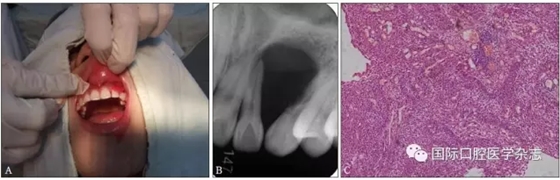

典型病例3 患者右下頜長(zhǎng)包1月,臨床初診為44牙根尖周囊腫,治療期間反復(fù)換藥,伴右下頜脹痛,根管充填后轉(zhuǎn)診外科行根尖囊腫刮治A術(shù),術(shù)后病理示:右下頜骨KCOT伴感染(圖3)。

A:術(shù)前全景片,43—45根方透射影像,邊緣可見骨白線;B:術(shù)前充填根尖片;C、D:蘇木精-伊紅染色切片,示腫瘤襯里上皮表面為波浪狀的不全角化層,基底層細(xì)胞柵欄狀排列,細(xì)胞核遠(yuǎn)離基底膜,C圖 × 100,D圖 × 400。

圖 3 右下頜骨KCOT

Fig 3 KCOT in the rightmandible

典型病例4 患者因左上頜牙齦長(zhǎng)包塊就診,X線片檢查發(fā)現(xiàn)左上頜22—23牙區(qū)明顯的透射區(qū),邊界清楚,相鄰牙根被推擠移位。手術(shù)切除后病理結(jié)果為成釉細(xì)胞瘤(圖4)。

A:術(shù)前臨床照片;B:術(shù)前X線片;C:蘇木精-伊紅染色切片,顯示成釉細(xì)胞瘤的病理特點(diǎn) × 100。

圖 4 成釉細(xì)胞瘤

Fig 4 Ameloblastoma